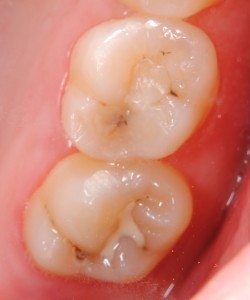

先日、従業員の口腔内診査を行った所、15年くらい前にセットした金属(インレー)と歯の境目に段差が生じていました。レントゲン診査では2次齲蝕の可能性がありましたが外してみて意外と虫歯が進行していて本人もびっくりしていました、虫歯を除去した後はコンポジットレジンで修復を行いました。

近年コンポジットレジンの材質が改良され噛み合わせの力がかかる部位への応用範囲が広がってきました。審美性、耐久性などセラミックには劣りますが、見た目もきれいですし(吸水性があるので長期使用で着色します)多くの場合1日で診療が終わります、噛み合わせや残存歯質の状態によっては適応できない場合もありますのでご相談下さい。治療は健康保険の適応内です。